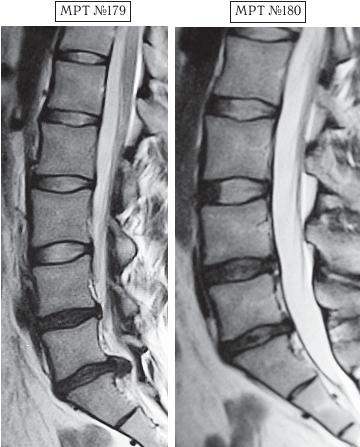

В первом случае у пациента, спустя определённое время, случилось сильное обострение. Сделали МРТ № 179, диагностировали секвестрированную грыжу межпозвонкового диска. Родители первого парня привели его на лечение ко мне в клинику. Так случилось, что в тот же день за консультацией обратились родители второго парня вместе с ним. Они также принесли снимки (МРТ № 183). У второго парня наблюдалась начальная стадия развития остеохондроза. В принципе ничего сложного, можно было подкорректировать, восстановить здоровье и этого юного пациента. Однако случилось так, что родители первого парня, в отличие от родителей второго, остановили свой выбор на клинике вертеброревитологии. Их сын прошёл курсы лечения данным методом и теперь за здоровье парня можно только порадоваться.

На МРТ № 179 наблюдается состояние поясничного отдела позвоночника (до лечения): сглаженность поясничного лордоза, протрузия (компенсированная спондилёзом) в сегменте LIV—LV, секвестрированная грыжа межпозвонкового диска в сегменте LV—SI, абсолютный стеноз позвоночного канала.

На МРТ № 180 — состояние поясничного отдела позвоночника после лечения методом вертеброревитологии: естественный физиологический лордоз поясничного отдела позвоночника, отсутствие секвестрированной грыжи межпозвонкового диска в сегменте LV—SI, отсутствие стеноза. Но самое интересное можно рассмотреть на МРТ № 181 и МРТ № 182.

На увеличенных фрагментах вышеприведенных снимков наблюдается состояние сегмента LV—SI до лечения (МРТ № 181) и после лечения методом вертеброревитологии (МРТ № 182).

На МРТ № 182 чётко прослеживается не только отсутствие секвестрированной грыжи межпозвонкового диска в сегменте LV—SI но и активный процесс восстановления межпозвонковых дисков (репаративная регенерация) в сегментах LIV—LV, LV—SI, и главное — процесс восстановления их пульпозных ядер. Так что можно образно сказать, что данный парень вытянул в жизни, не без помощи своих родителей, счастливый билет: он уже практически здоров, грыжа диска устранена без операции и биомеханика позвоночника восстановлена, а для молодого организма это немаловажный фактор. Но главное, он получил бесценный, собственный опыт того, что компьютер компьютером, а собственное здоровье ценнее всего и его надо беречь смолоду.